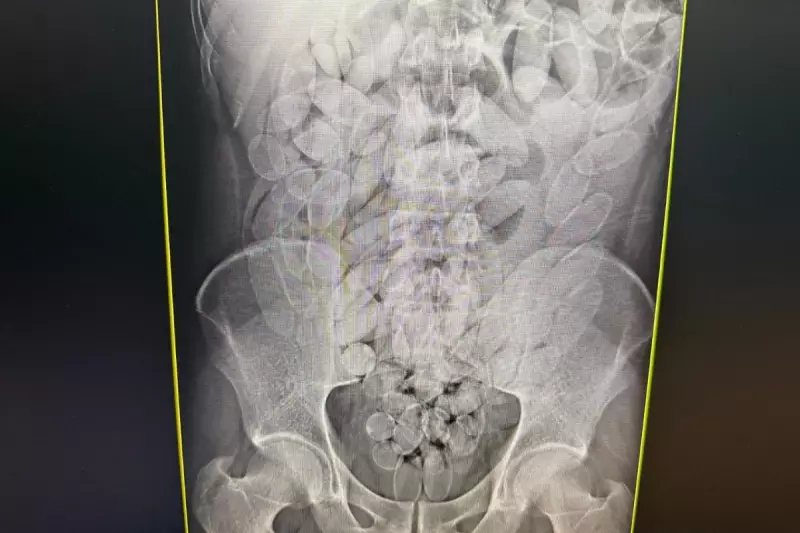

Uma operação da Polícia Federal em Corumbá, Mato Grosso do Sul, resultou na prisão de oito cidadãos bolivianos que transportavam cocaína de forma extremamente arriscada. Os suspeitos haviam ingerido 645 cápsulas contendo a droga, totalizando aproximadamente 7 quilos de cocaína pronta para distribuição no mercado ilegal.

O método de ingestão das cápsulas representa um perigo mortal para os transportadores, conhecidos como "mulas" do tráfico. Qualquer rompimento das embalagens no estômago ou intestino pode causar overdose imediata e levar à morte.

Os presos passarão por avaliação médica para garantir que todas as cápsulas sejam eliminadas de seus organismos de forma segura, sob supervisão de profissionais de saúde.